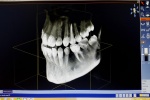

Technologia 3D = Bezpieczeństwo

(zdjęcie 1 z 2)